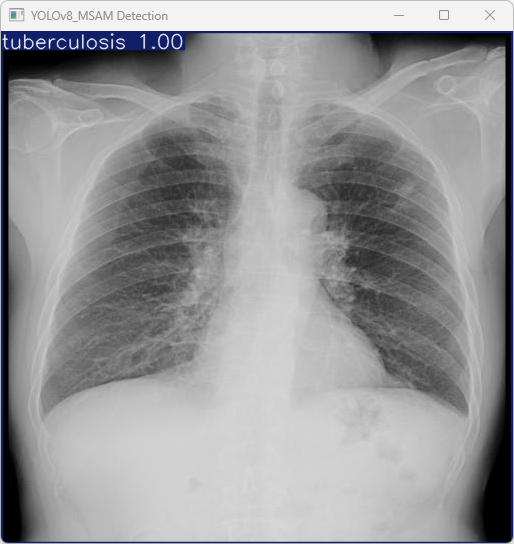

图15 YOLOv8_MSAM Detection Result

模型成功识别了输入图像中的结核病(tuberculosis),并且推理过程速度较快,其中预处理、推理和后处理时间分别为5.1ms、6.5ms和135.2ms,显示出该模型在目标检测任务中的高效性。